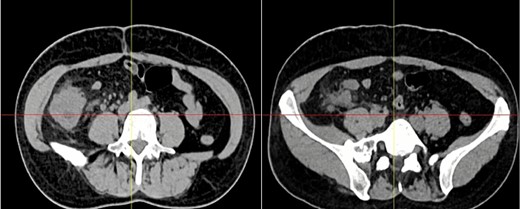

Complementary exams revealed normal leukocytes (9.86 × 109/l) without neutrophilia and an elevated C-reactive protein. Due to the pain and the palpable mass, a contrast-enhanced computed tomography (CT) was needed. It revealed a 15 × 15 cm heterogeneous mass that compromised the cecum and ileocecal valve; it also had mesentery involvement, with focal strands radiating into the mesenteric fat (Fig. 1).

Abdominal CT, the mass is seen in the cecum and ileocecal valve.